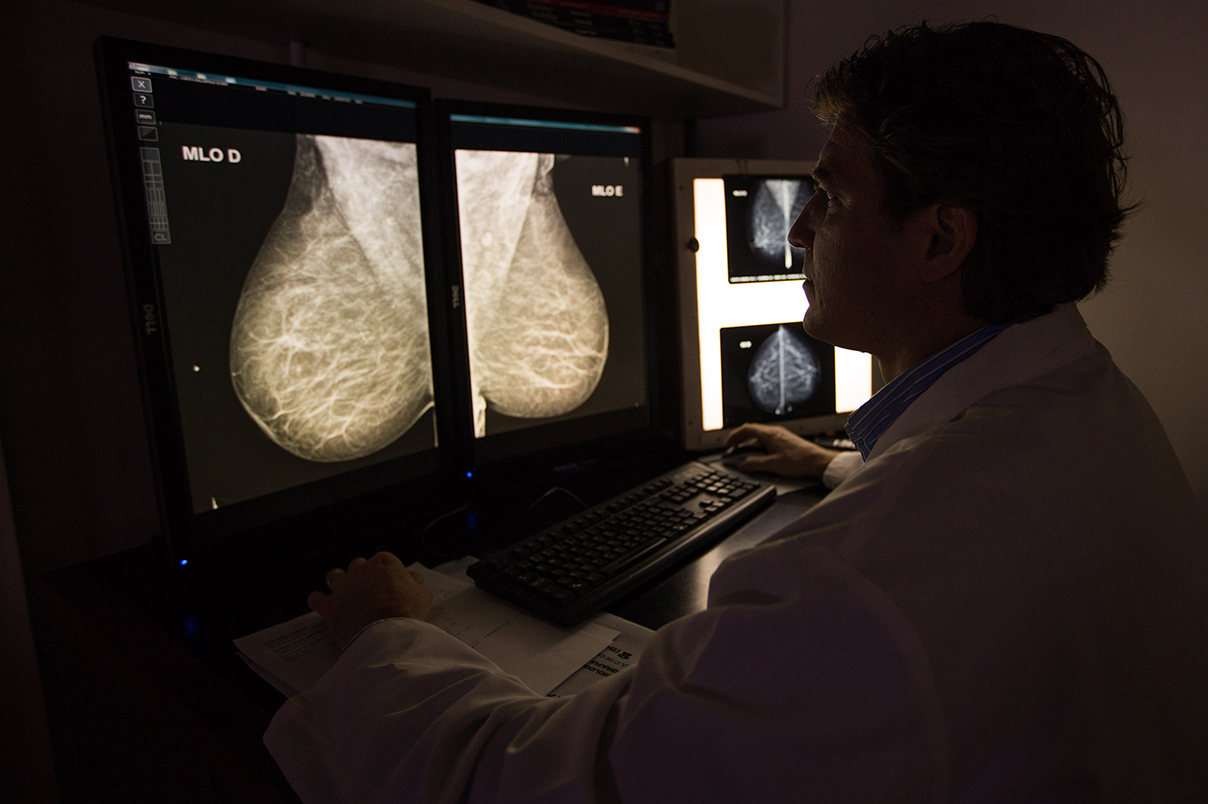

Mamografia Digital

Tipo específico de exame de mama que usa raios-x em baixa dose para demonstrar as estruturas internas das mamas e detectar sinais de câncer precocemente.